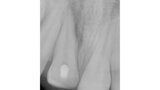

Endodontické ošetření horního středního řezáku s atypickou anatomií